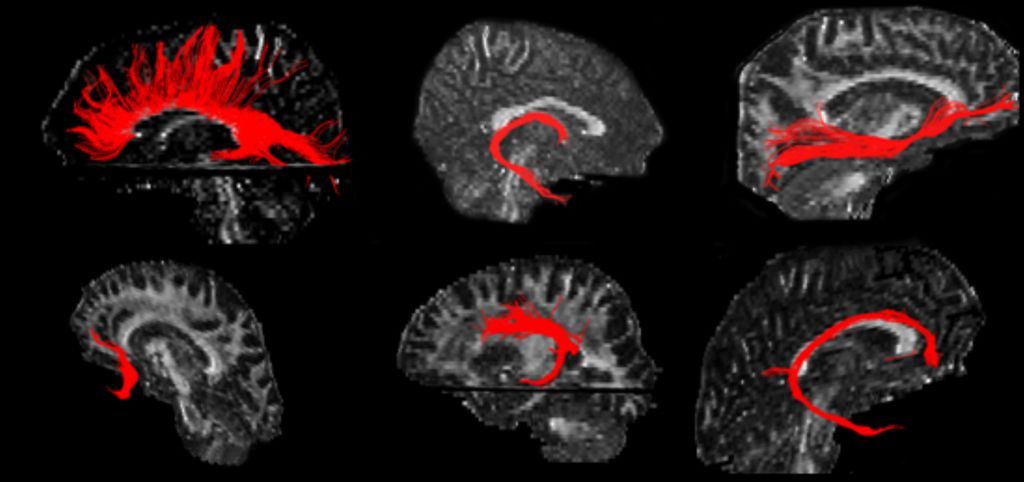

The serial MRI images here were obtained on a biyearly basis in a patient with relapsing-remitting MS. The images reveal an increasing number of plaques within hemispheric white matter, an increase in the number and size of black holes, and progressive brain volume loss.

Image courtesy of A. Rovira